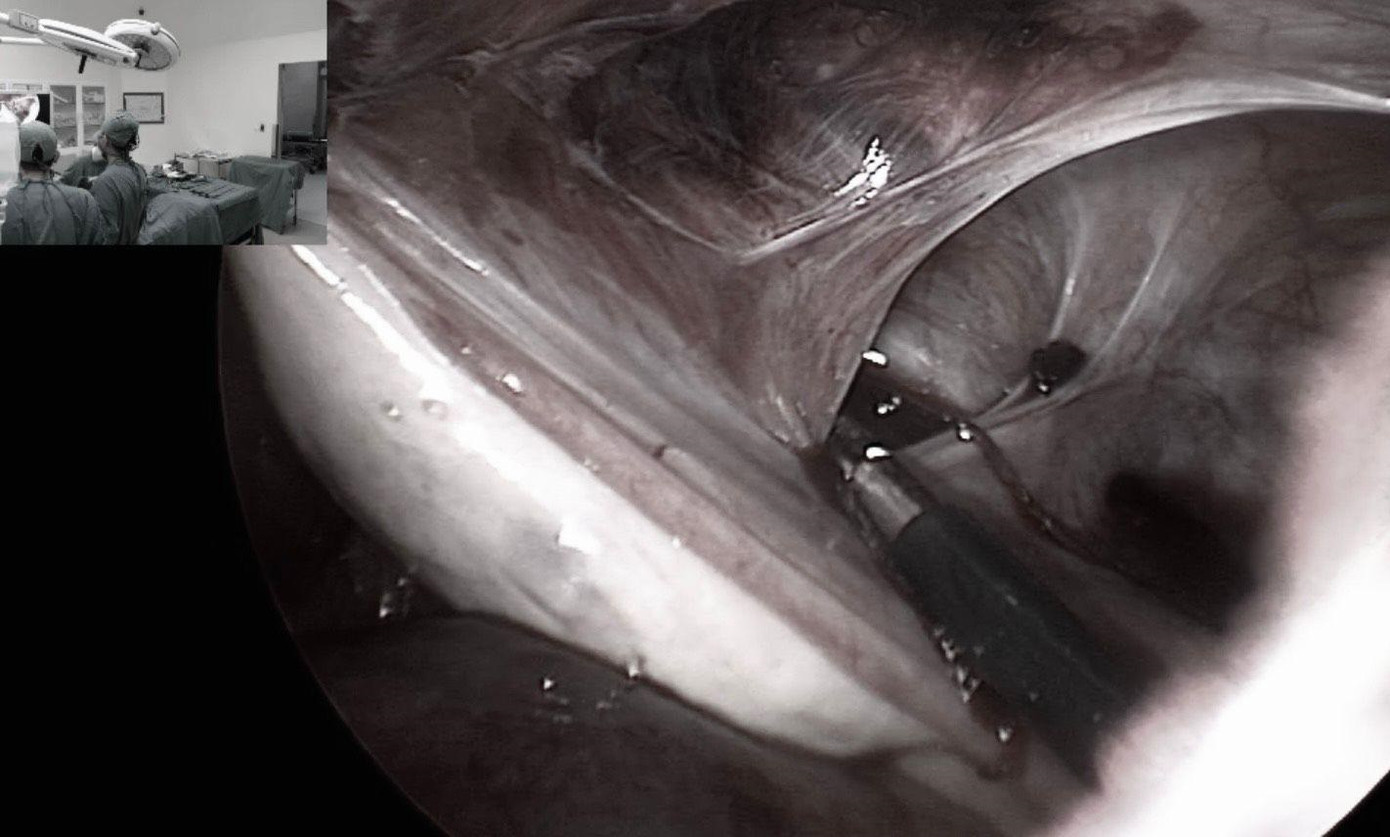

| Các bác sĩ thực hiện cuộc nội soi can thiệp tình trạng dính buồng trứng cho bệnh nhân |

Trong quá trình phẫu thuật bác sĩ phát hiện buồng trứng và vòi trứng bên trái của bệnh nhân dính lên thành bụng. Vị trí bị dính tạo thành một lỗ hình bầu dục có đường kính khoảng 3cm như chiếc thòng lọng, khi các quai ruột chui qua đã bị treo lên và kẹt lại gây tắc ruột.

Sau khi giải phóng các quai ruột, ê kíp phẫu thuật cũng tiến hành gỡ dính buồng trứng, vòi trứng. Quá trình thám sát toàn bộ ổ bụng, các bác sĩ ghi nhận thêm tại vùng bụng dưới bên phải của bệnh nhân, mạc nối lớn cũng bị dính lên thành bụng tạo thành một lỗ tương tự bên trái nên tiến hành gỡ dính. Sau phẫu thuật, sức khỏe của bệnh nhân đã bình phục tốt.